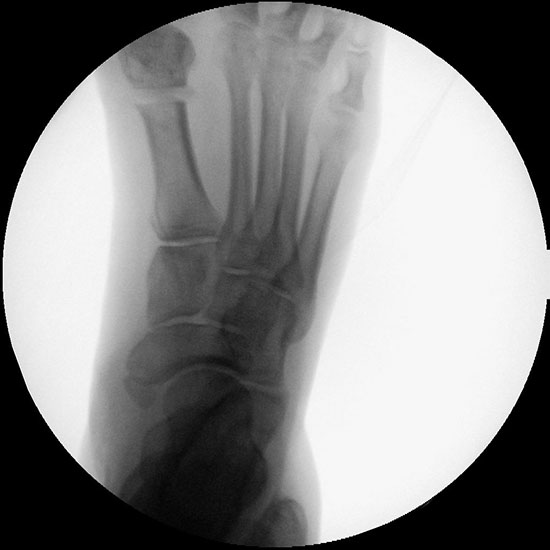

• Röntgenkontrollen (Vorfuß in zwei Ebenen) postoperativ und ggf. nach zwei Wochen jeweils ohne Belastung. Abschlusskontrolle zur Dokumentation der knöchernen Konsolidierung nach sechs Wochen unter voller Belastung.